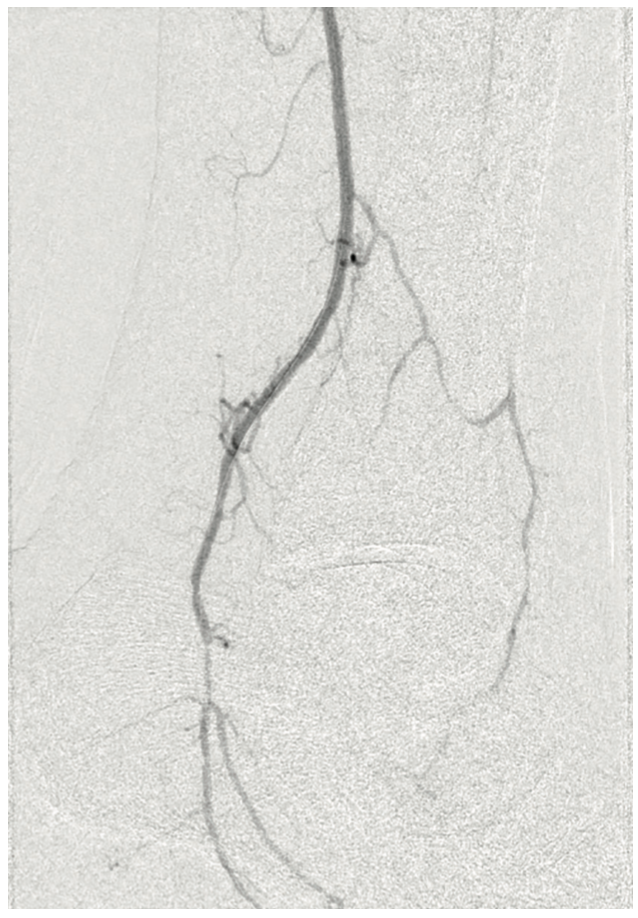

The patient was heparinized. A long 6 French Destination sheath (Terumo Interventional Systems) was used to cannulate the femoral-popliteal artery with an .035-inch system. We then selectively cannulated the posterior tibial artery with an .014-inch Grand Slam wire (Asahi Intecc). Using an .014-inch catheter and wire, we were able to pass through the distal posterior tibial artery stenosis into the pedal vessels. We started with a 2.0 mm plain balloon (POBA), resulting in recoil (Figures 3-4). We then used a 2.5 mm diameter Serranator PTA Serration Angioplasty Balloon (Cagent Vascular) (Figure 5) and achieved significant lumen gain without recoil. The peroneal artery lesion was also treated with angioplasty. The posterior tibial artery was considered to be the most important for wound healing, as the peroneal artery mostly terminated at the ankle level and the posterior tibial artery had strong dominant flow into the left foot. In addition, the anterior tibial and dorsalis pedis pathway was chronically occluded and essentially clinically nonexistent.

The final imaging of the posterior tibial artery demonstrated a surprisingly positive angiographic result with brisk blood flow and was clinically satisfactory (Figure 6). We were encouraged with this outcome, and optimistic for eventual wound healing.